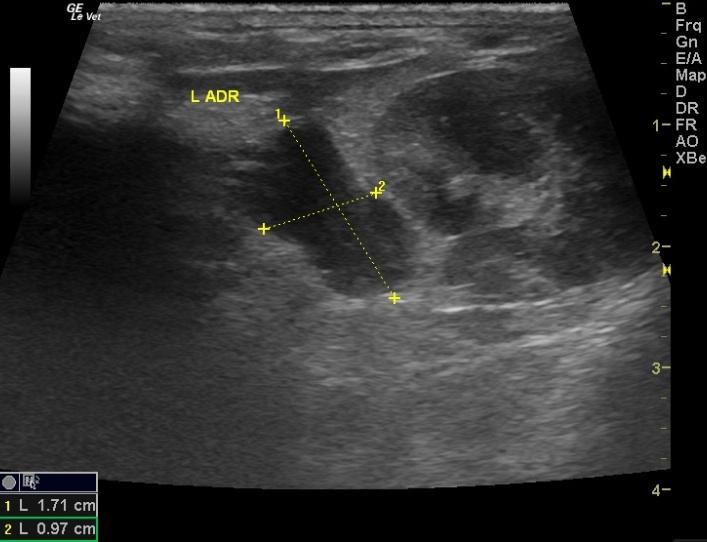

A 5-year-old FI Guinea Pig was presented with history of flank alopecia and weight loss. CBC was within normal limits. The only abnormality on blood chemistry was a slight ALT elevation.